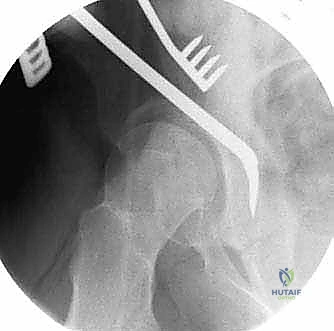

2. سلسلة قطع العظام (The 5 Osteotomies)

يكمن سر نجاح جراحة PAO في إجراء خمسة قطوع عظمية منفصلة حول الحُق، لتحريره بالكامل عن باقي الحوض، مع ترك العمود الخلفي سليماً كدعامة أساسية.

القطع الأول: القطع الإسكي غير المكتمل (Incomplete Ischial Osteotomy)

باستخدام إزميل خاص ذو زاوية (Angled Osteotome)، يتم إجراء قطع في عظم الإسك أسفل الحُق مباشرة (في الأخدود تحت الحُقي). يتم هذا القطع بتوجيه الأشعة السينية (Fluoroscopy) لضمان عدم اختراق المفصل. يحرص الدكتور هطيف على إبعاد العصب الوركي والأوعية السدادية بأمان تام.